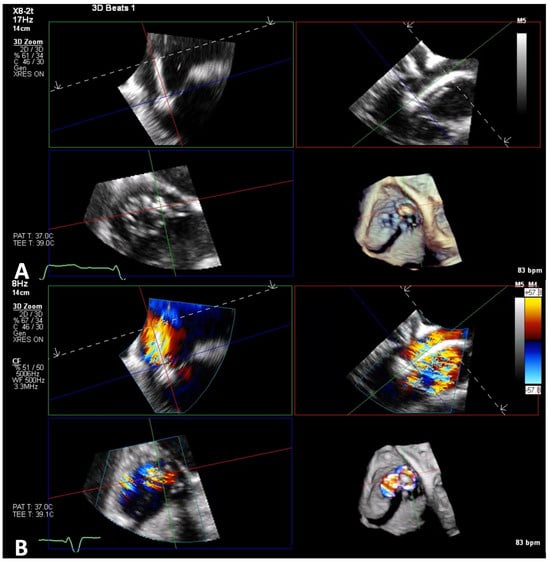

6. Intraprocedural Guidance

6.1. TEE-Guided Tricuspid TEER

- Wang, T.K.M.; Harb, S.C.; Miyasaka, R.L.; Wagener, J.; Krishnaswamy, A.; Reed, G.K.; Kapadia, S.R. Live Three-Dimensional Multiplanar Reconstruction Imaging Guidance for Concomitant Mitral and Tricuspid Valve Repairs Using the MitraClip. CASE Cardiovasc. Imaging Case Rep. 2020, 4, 119–126. [Google Scholar] [CrossRef]